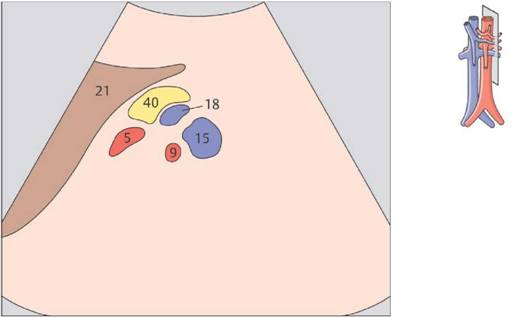

ЦИФРАМИ ОБОЗНАЧЕНЫ

1 Аорта

2 Подвздошная артерия

3 Чревный ствол

4 Печеночная артерия

5 Селезеночная артерия

6 Левая желудочная артерия

7 Верхняя брыжеечная артерия

8 Правая почечная артерия

9 Левая почечная артерия

10 Нижняя половая вена

11 Левая печеночная вена

12 Средняя печеночная вена

13 Правая печеночная вена

14 Правая почечная вена

15 Левая почечная вена

16 Подвздошная вена

17 Воротная вена

18 Селезеночная вена

19 Верхняя брыжеечная вена

20 Правая доля печени

21 Левая доля печени

22 Квадратная доля

23 Хвостатая доля

24 Круглая связка

25 Венозная связка

26 Латеральный сегмент

27 Медиальный сегмент

28 Передний сегмент

29 Задний сегмент

30 Желчный пузырь